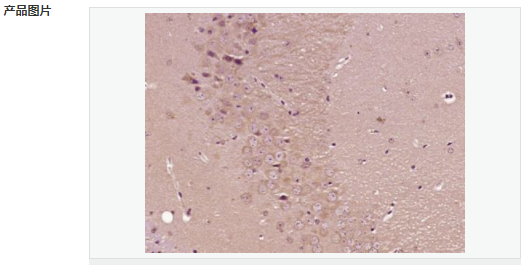

交叉反應:Mouse,Rat(predicted:Human,Pig) 推薦應用:IHC-P,IHC-F,IF,ELISA

| 產(chǎn)品應用 | ELISA=1:5000-10000 IHC-P=1:100-500 IHC-F=1:100-500 IF=1:100-500 (石蠟切片需做抗原修復) not yet tested in other applications. optimal dilutions/concentrations should be determined by the end user. |